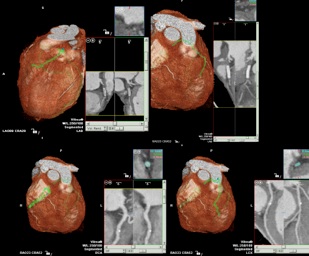

Durch die hochauflösende Aufnahmetechnik gelingt es die

Koronargefäße, Verkalkungen im Bereich der Koronargefäße  sowie

Bypassgefäße und weitere wichtige Herzstrukturen darzustellen.

*  Darstellung der Koronararterien

*  Darstellung aortokoronarer Bypässe